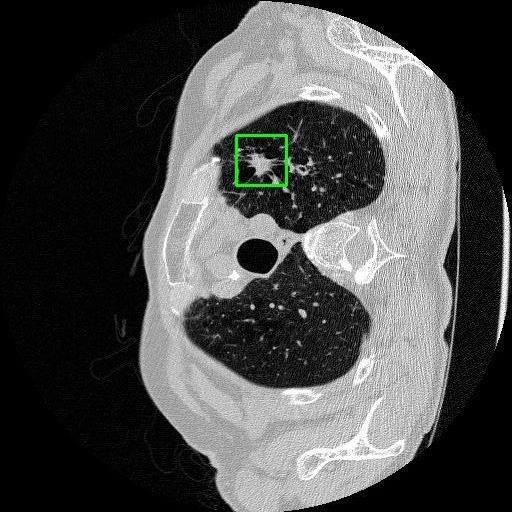

We developed an AI-based system using deep learning models for analyzing lung CT scans to detect and classify pulmonary nodules. We chose the YOLOv11 architecture for its enhanced object detection capability and adapted it specifically for medical imaging, incorporating pixel-level precision and severity classification.

Classification into three severity levels with colored bounding boxes.

Designed a severity classification system that categorizes nodules into null, moderate, and severe using colored bounding boxes, assisting in rapid clinical decision-making.